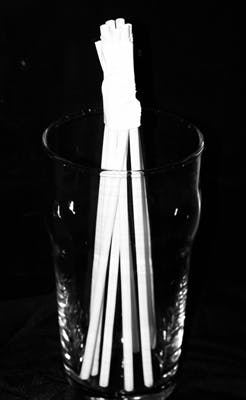

Figure 5: Post bundle

Figure 7: Acid total-etch treatment of tooth No. 10

For this case, the Rebilda Post GT System (Voco) was used (figures 3 and 4). The material consists of a series of fine glass fiber–reinforced posts that are bundled together inside a color-coded sleeve. As these posts were cemented, the sleeve was removed prior to light polymerization of the core material. This allowed the spreading out of the fibers within the core material as the case demanded (figure 5). Green-sleeve posts, which bundle nine fine posts that are 1.2 mm in diameter collectively, were selected. They were tried in to verify a passive fit (figure 6).

Figure 8: Adhesive application